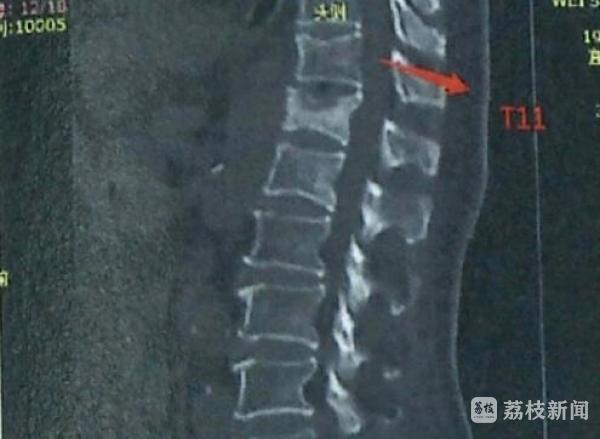

经交警部门认定,席某承担事故的主要责任,袁某承担事故的次要责任,巍女士无责任,经鉴定,巍女士构成九级伤残,定残时71周岁。